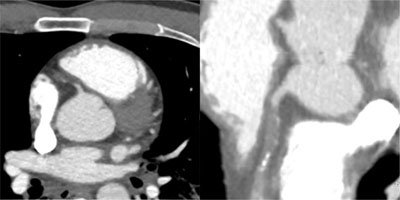

Figure 4

Spiral acquisition trauma CT of the thorax and abdomen after intravenous injection of 100 ml iodized contrast. Focus on the heart showing dissection and complete occlusion of the RCA. Left image: axial view, right image: curved view.